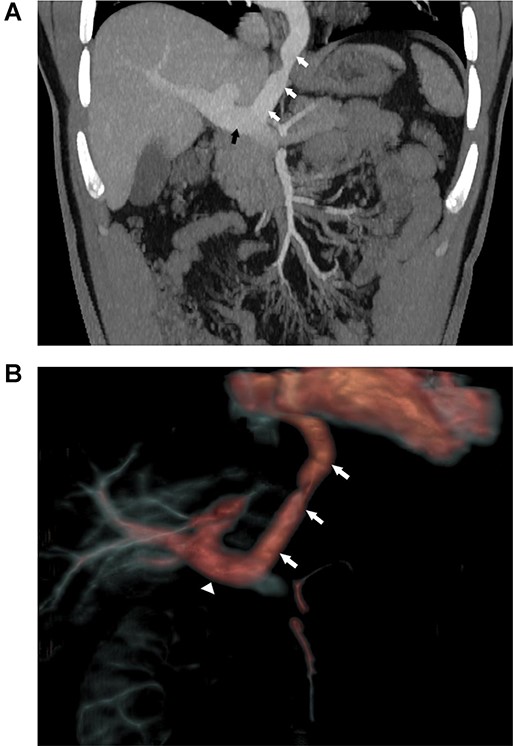

At 28-years old, a transverse laparotomy was performed in the mid-upper abdomen, the hepato-duodenal ligament was opened to expose the portal vein and the remnant VV was identified (Fig. 2). The vessel was occluded with vascular clamps and hemodynamic parameters were closely monitored. Since clamp occlusion did not produce any variation of the hemodynamic status or cardiac electrophysiology, the proximal aspect of the vessel was divided at the level of the diaphragm using an Echelon Flex™ (Ethicon, USA) vascular stapler. The distal end was subsequently ligated at the portal vein using 3-0 absorbable ties and over-sewn with 4-0 non-absorbable monofilament. The vessel was fully excised.

Intra-abdominal exposure of the infra-diaphragmatic portion of the vessel following ligation of a small left lateral tributary.